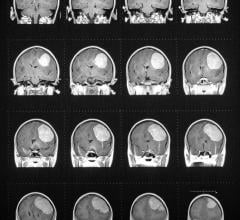

Aug. 12, 2025 — ZAP Surgical Systems, Inc. recently announced the treatment of the 5,000th patient using its ZAP-X ...